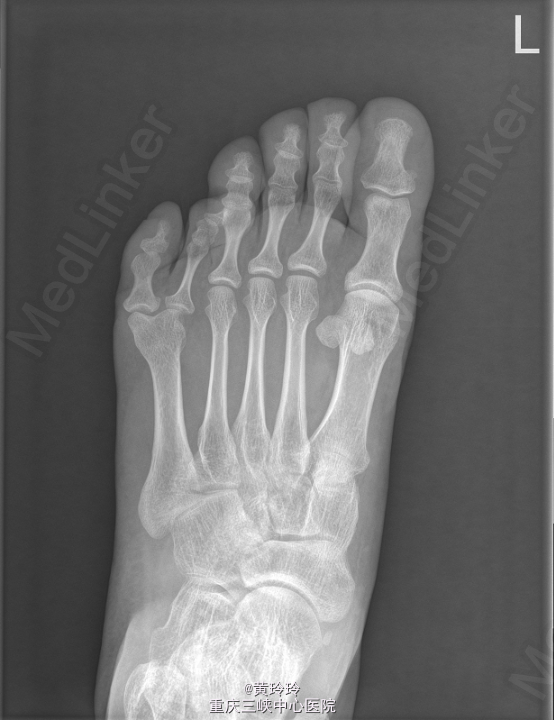

患者,女,32岁,因“ 发现左足多趾20年余 ”入院。

查体: 左足第四趾与第五趾之间长出一趾. X线提示左足第5多趾畸形。